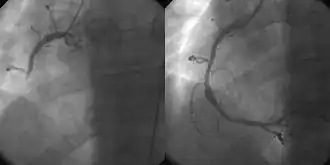

Angiografia coronária e angioplastia no infarto agudo do miocárdio (esquerda: Artéria Coronária Direita [ACD] fechada, direita: dilatada com sucesso)

As principais vantagens da utilização da abordagem de cardiologia intervencionista ou radiologia são evitar cicatrizes e dores e longa recuperação pós-operatória. Além disso, o procedimento de cardiologia intervencionista de angioplastia primária é agora o padrão ouro de tratamento para um infarto agudo do miocárdio. Envolve a extração de coágulos de artérias coronárias ocluídas e a implantação de stents e balões através de um pequeno orifício feito em uma artéria principal.[1][2]